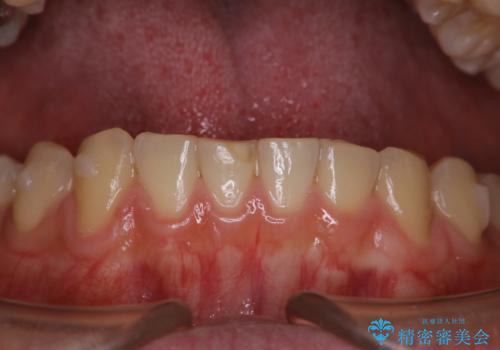

歯科医院にて染め出しをして歯磨き指導と専門的なクリーニング(PMTC)

- 久しぶりの来院のためクリーニング希望とのことでした。染め出しを行い、歯ブラシ指導とPMTC30分コースを行いました。

染め出し液を使ってプラークを染め出すことにより、普段の歯みがきで磨き残している場所を目で確かめることができます。

日々の歯磨きを上達するには、まずどこが磨けていないか認識することが大切です。